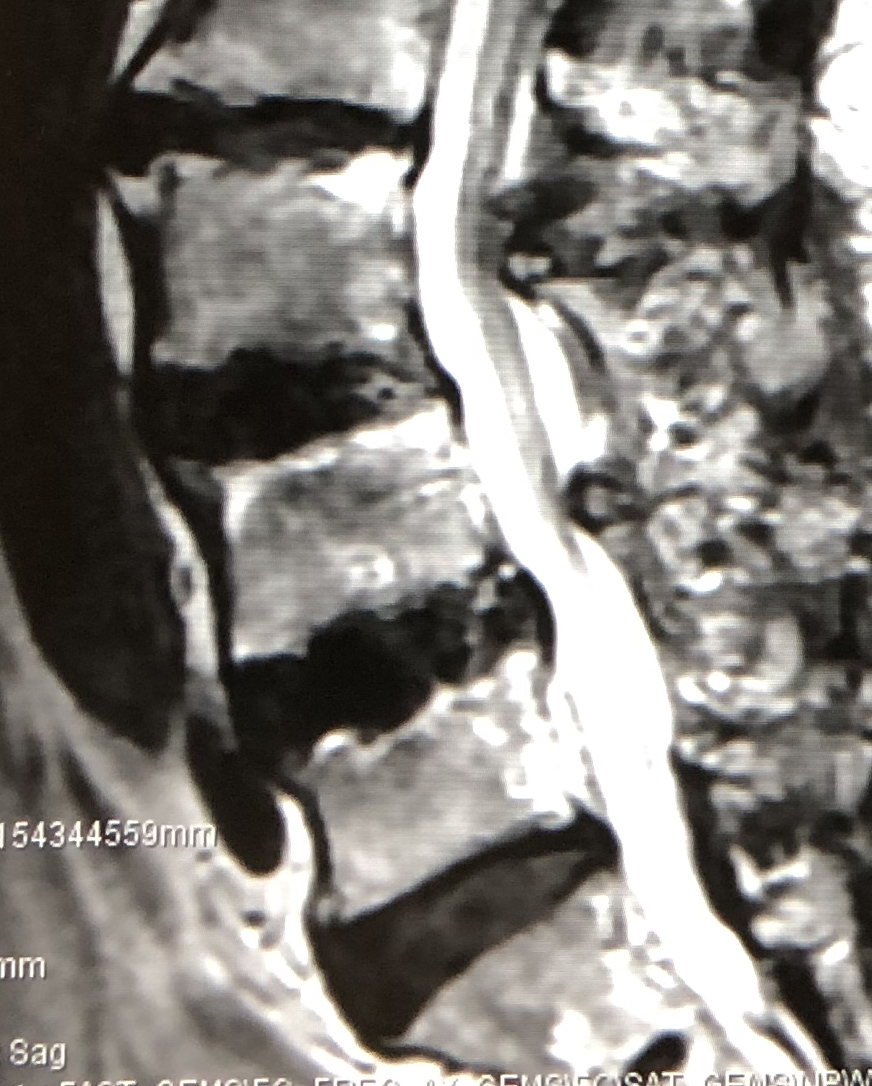

脊椎のすべりにより高度の脊柱管狭窄がある場合に、後方からすべりの矯正や神経の除圧が同時に行える手術です。

| 術前 | 術後 | |

| MRI |

|